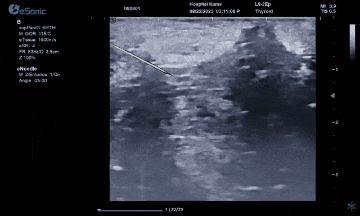

hjc888黄金城官网医疗(ESI)表示,其最新的人工智能功能可以帮助到医疗机构的工作效率,功能包括,实时、动态、快速自动识别病灶,良恶性病灶概率预测,甲状腺结节和乳腺的二维灰阶动态自动实时检测需求,提供多个结节动态检测轮廓框。实时获取多幅具备临床特征(大小、属性等)的结节切面,同时提供当前切面所示结节的结节大小、属性特征、TI-RADS 分级。

对于甲状腺结节相关的自动检测功能,甲状腺结节病灶检出率≥95%,良恶性分类灵敏度≥90%、良恶性分类特异度≥85%。